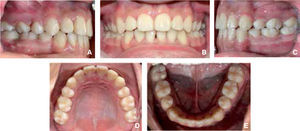

En el análisis intraoral se observa la línea media desviada hacia la izquierda, apiñamiento severo anterosuperior y anteroinferior, incisivo central superior izquierdo proinclinado, incisivo lateral derecho superior borde a borde con el canino y un overjet y overbite de 6 y 1mm respectivamente (Figura 2).

Del lado derecho se observa la línea media desviada hacia la izquierda, apiñamiento severo anterosuperior y anteroinferior, el incisivo superior izquierdo proinclinado, el incisivo lateral derecho superior borde a borde con el canino y el segundo molar con inclinación mesial y en infraoclusión (Figura 2). Del lado izquierdo se observa clase I molar y clase I canina, además del incisivo superior izquierdo palatinizado (Figura 2).